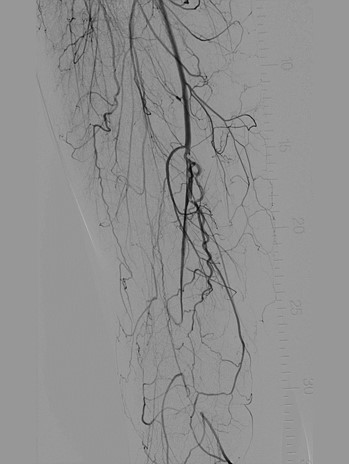

Режим Dynamic trace

Dynamic trace – режим дослідження кінцівок, передбачає рух деки столу за напрямком поширення контрастної речовини по периферичних судинах в режимі рентгенографії.